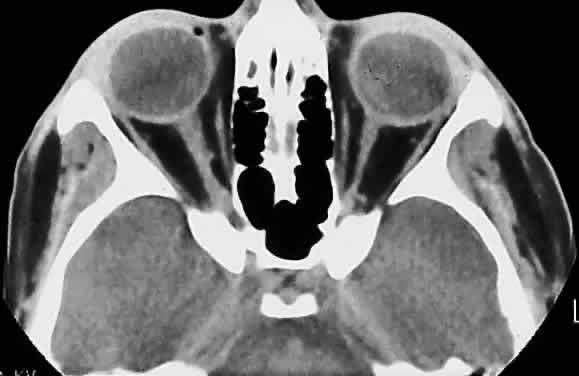

Fig. 14. Computed tomographic scan of head, showing hypoplastic left optic nerve.

In optic nerve hypoplasia, the optic disc appears gray and is about half its normal size but retinal vessels are present because the optic stalk is invaginated by mesoderm. The optic foramen is also small. Clinically, there may be strabismus, nystagmus, and decreased visual acuity. Severe cerebral abnormalities may be present but the hypoplastic nerve may be the sole abnormality.